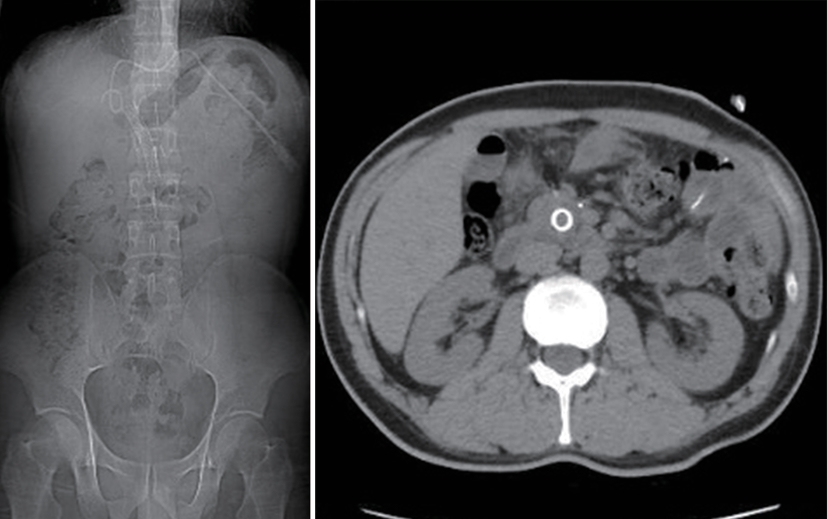

Value of internal stratification analysis of abdominal wall muscles in predicting complications after orthotopic liver transplantation

Xin SHI, Chongxiao LIANG, Bei ZHANG, Jiping WANG

2025, 41(2): 314-321. DOI: 10.12449/JCH250218

Abstract(738) HTML (351) PDF (3265KB)(53)

Abstract:

Objective  To divide the muscle into different subzones according to different density ranges using the stratified analysis on the basis of myosteatosis, and to investigate the effect of muscle density changes on complications (Clavien-Dindo grade ≥Ⅲ) after orthotopic liver transplantation (OLT).  Methods  A retrospective analysis was performed for the medical records of 145 patients who underwent OLT in The First Hospital of Jilin University from May 2013 to September 2020, and with the plain CT scan images of the largest level of lumbar 3 vertebrae of each patient as the original data, Neusoft Fatanalysis software was used to measure related muscle parameters. The independent-samples t test was used for comparison of normally distributed continuous data between two groups, and the Mann-Whitney U test was used for comparison of non-normally distributed continuous data between two groups. The chi-square test or Fisher test was for comparison of categorical data between two groups. RIAS software was used to extract clinical features and perform analysis and modeling, and three machine learning models of logistic regression (LR), support vector machine (SVM), and random forest (RFC) were constructed. The receiver operating characteristic (ROC) curve, the calibration curve, and the decision curve were plotted for each model to calculate the area under the ROC curve (AUC), sensitivity, specificity, precision, F1 score, and accuracy.  Results  The three machine learning models of LR-C, SVM-C, and RFC-C were established based on the 7 clinical features before muscle stratification analysis, among which the RFC-C model had an AUC of 0.803, a sensitivity of 0.588, and a specificity of 0.778 in the test set. Among the models of LR-CS, SVM-CS, and RFC-CS established based on the 16 clinical features after muscle stratification analysis, the LR-CS and SVM-CS models had an AUC of 0.852 in the test set, with a sensitivity of 0.765 and 0.706, respectively, and a specificity of 0.889 and 0.926, respectively. Comparison of the AUC, sensitivity, specificity, precision, F1 score, and accuracy of each model in the test set before and after muscle stratification analysis showed that there were improvements in the parameters of the predictive model after muscle stratification analysis. Comparison of the decision curves and calibration curves of each predictive model showed that the LR-CS and SVM-CS models had good efficacy in predicting postoperative complications (Clavien-Dindo grade≥Ⅲ) in OLT patients.  Conclusion  On the basis of myosteatosis, the division of the muscle into different subzones according to different densities using the stratified analysis has a certain value in predicting postoperative complications in patients with OLT.